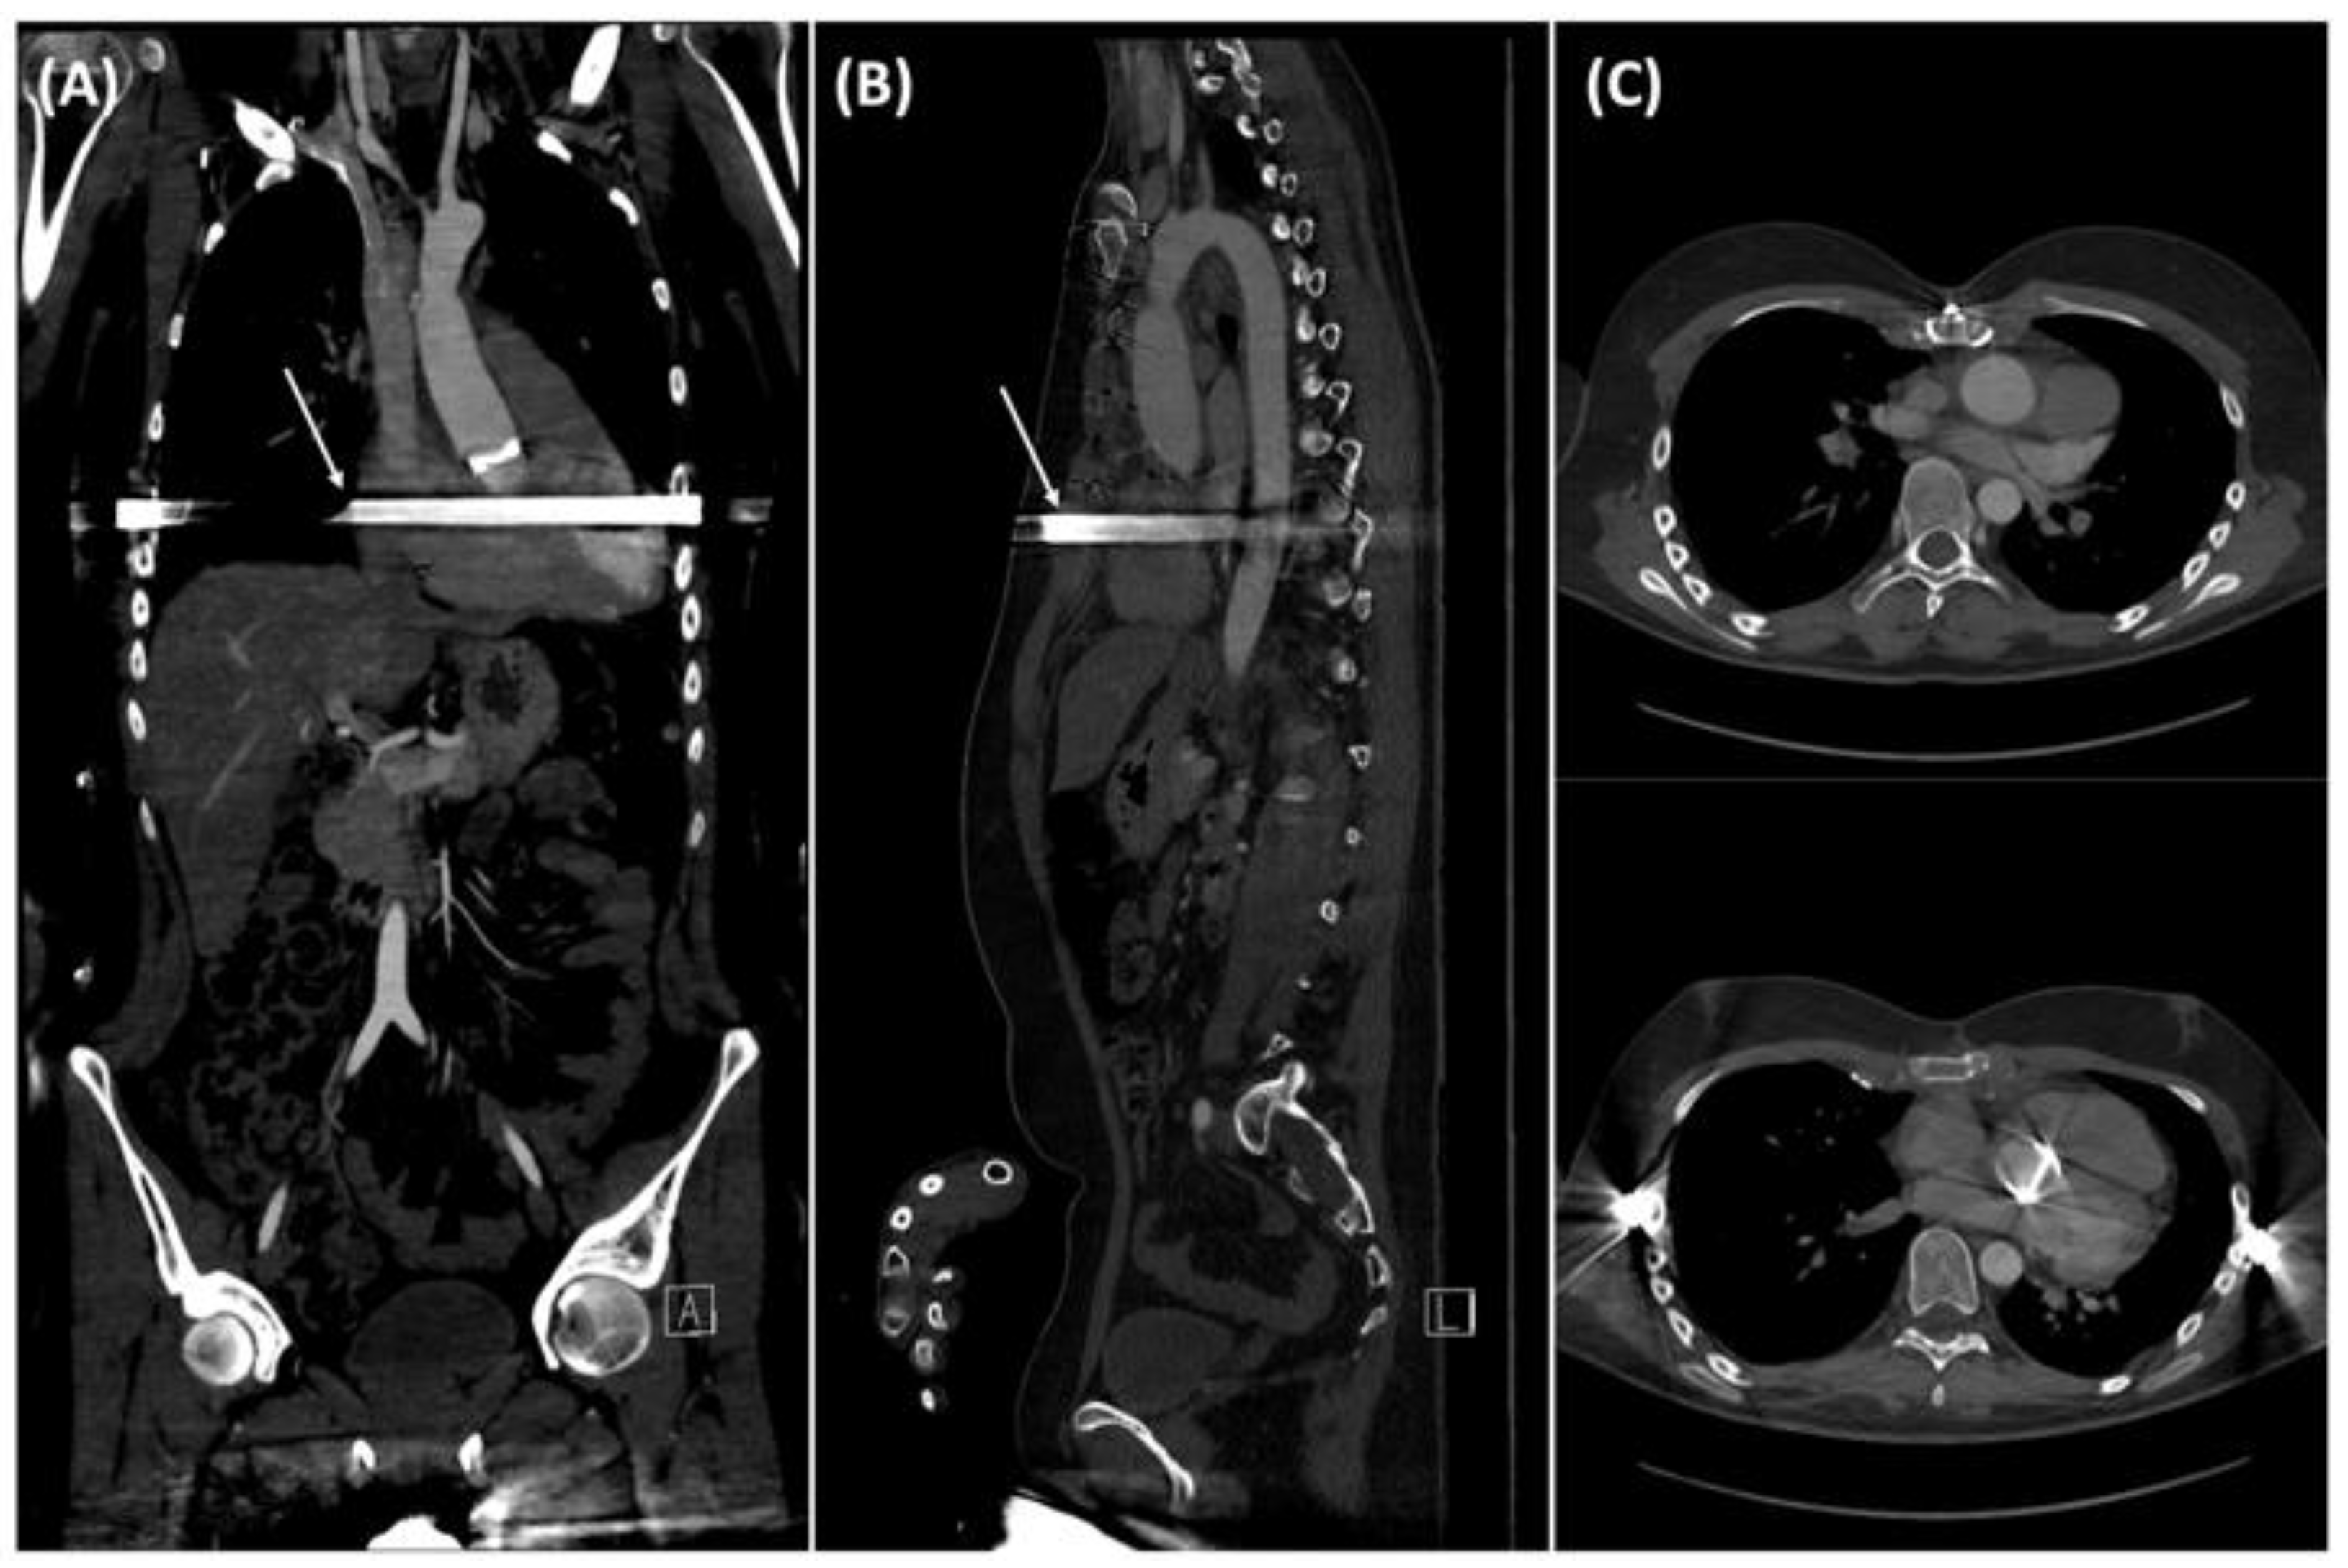

2. Case Description